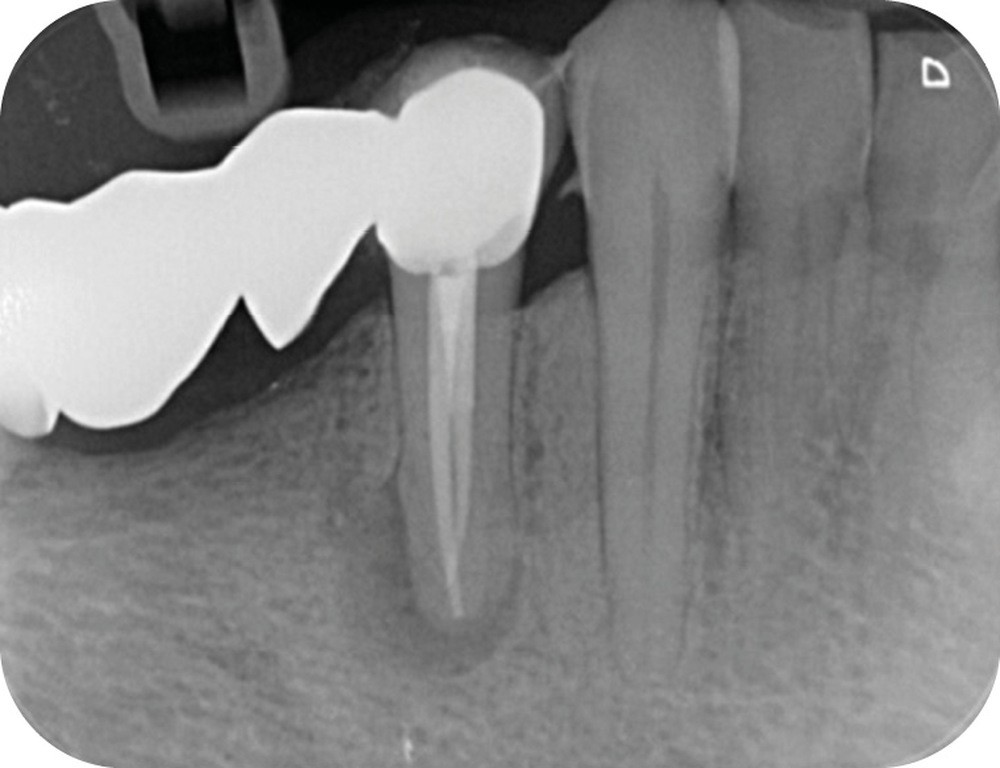

La mise en forme canalaire à travers un bridge impose des contraintes instrumentales importantes, et nécessite une analyse préopératoire minutieuse. Ici, nous avons eu recours à des limes de pré-élargissement mécanisé afin de sécuriser la trajectoire canalaire (fig. 7). Une préparation corono-apicale jusqu’à une finition apicale 25-6 % a ensuite été choisie afin d’optimiser le flux d’irrigant dans le tiers apical. À la suite de l’ajustage des maîtres cônes et d’un protocole d’irrigation finale (EDTA & NaOCl), une obturation selon la technique de condensation verticale à chaud est réalisée, puis la patiente est revue pour une restauration composite de la face occlusale (fig. 8, 9). Le contrôle à six mois révèle la disparition de la symptomatologie ainsi que des signes radiologiques de cicatrisation apicale (fig. 10).